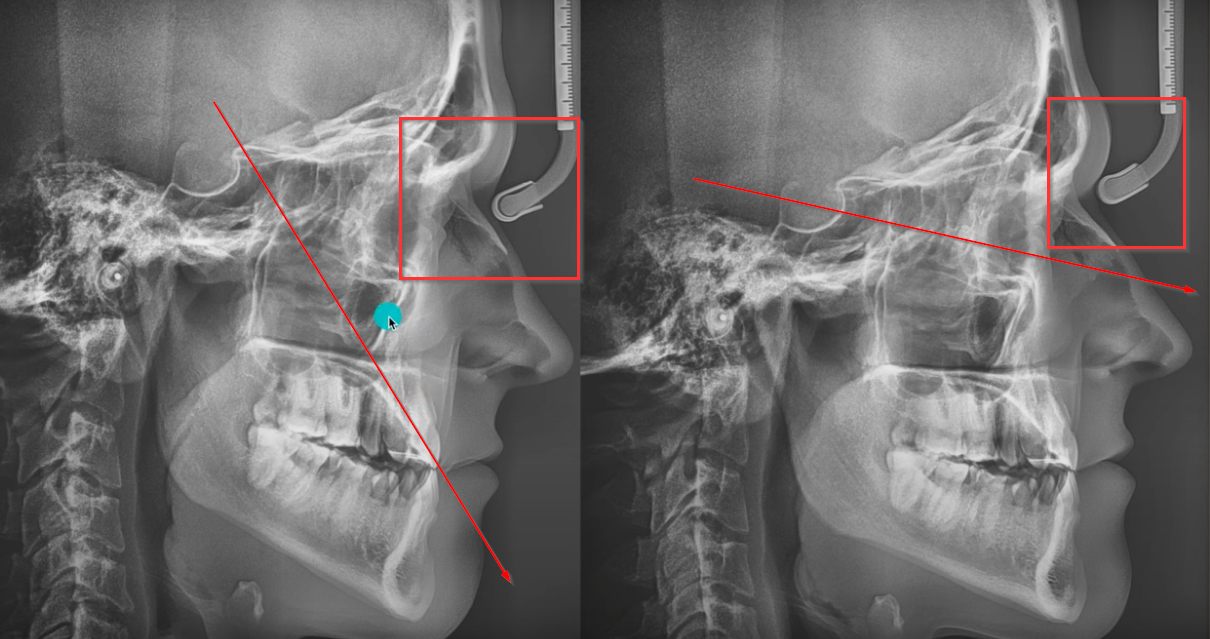

Results start at 5:55

best evidence I found so far:

that's how he looks like:This is some salludon type mewing shit. How did his browridge move forward

Results start at 5:55

best evidence I found so far:

its a timelapse from 17 -23 yo , of course his jaw will grow if he has the genetics for itThis is some salludon type mewing shit. How did his browridge move forward

He said in the thread he only started at 21 and all the change from 17 to 23 was in those 2 yearsits a timelapse from 17 -23 yo , of course his jaw will grow if he has the genetics for it

Yes but if you tilt your head this isn’t goint to push your molar forward lolhere we go again with the 'mewing'

his head is titled in the first pic and straight on the second, you can clearly see it on pic

View attachment 2121582